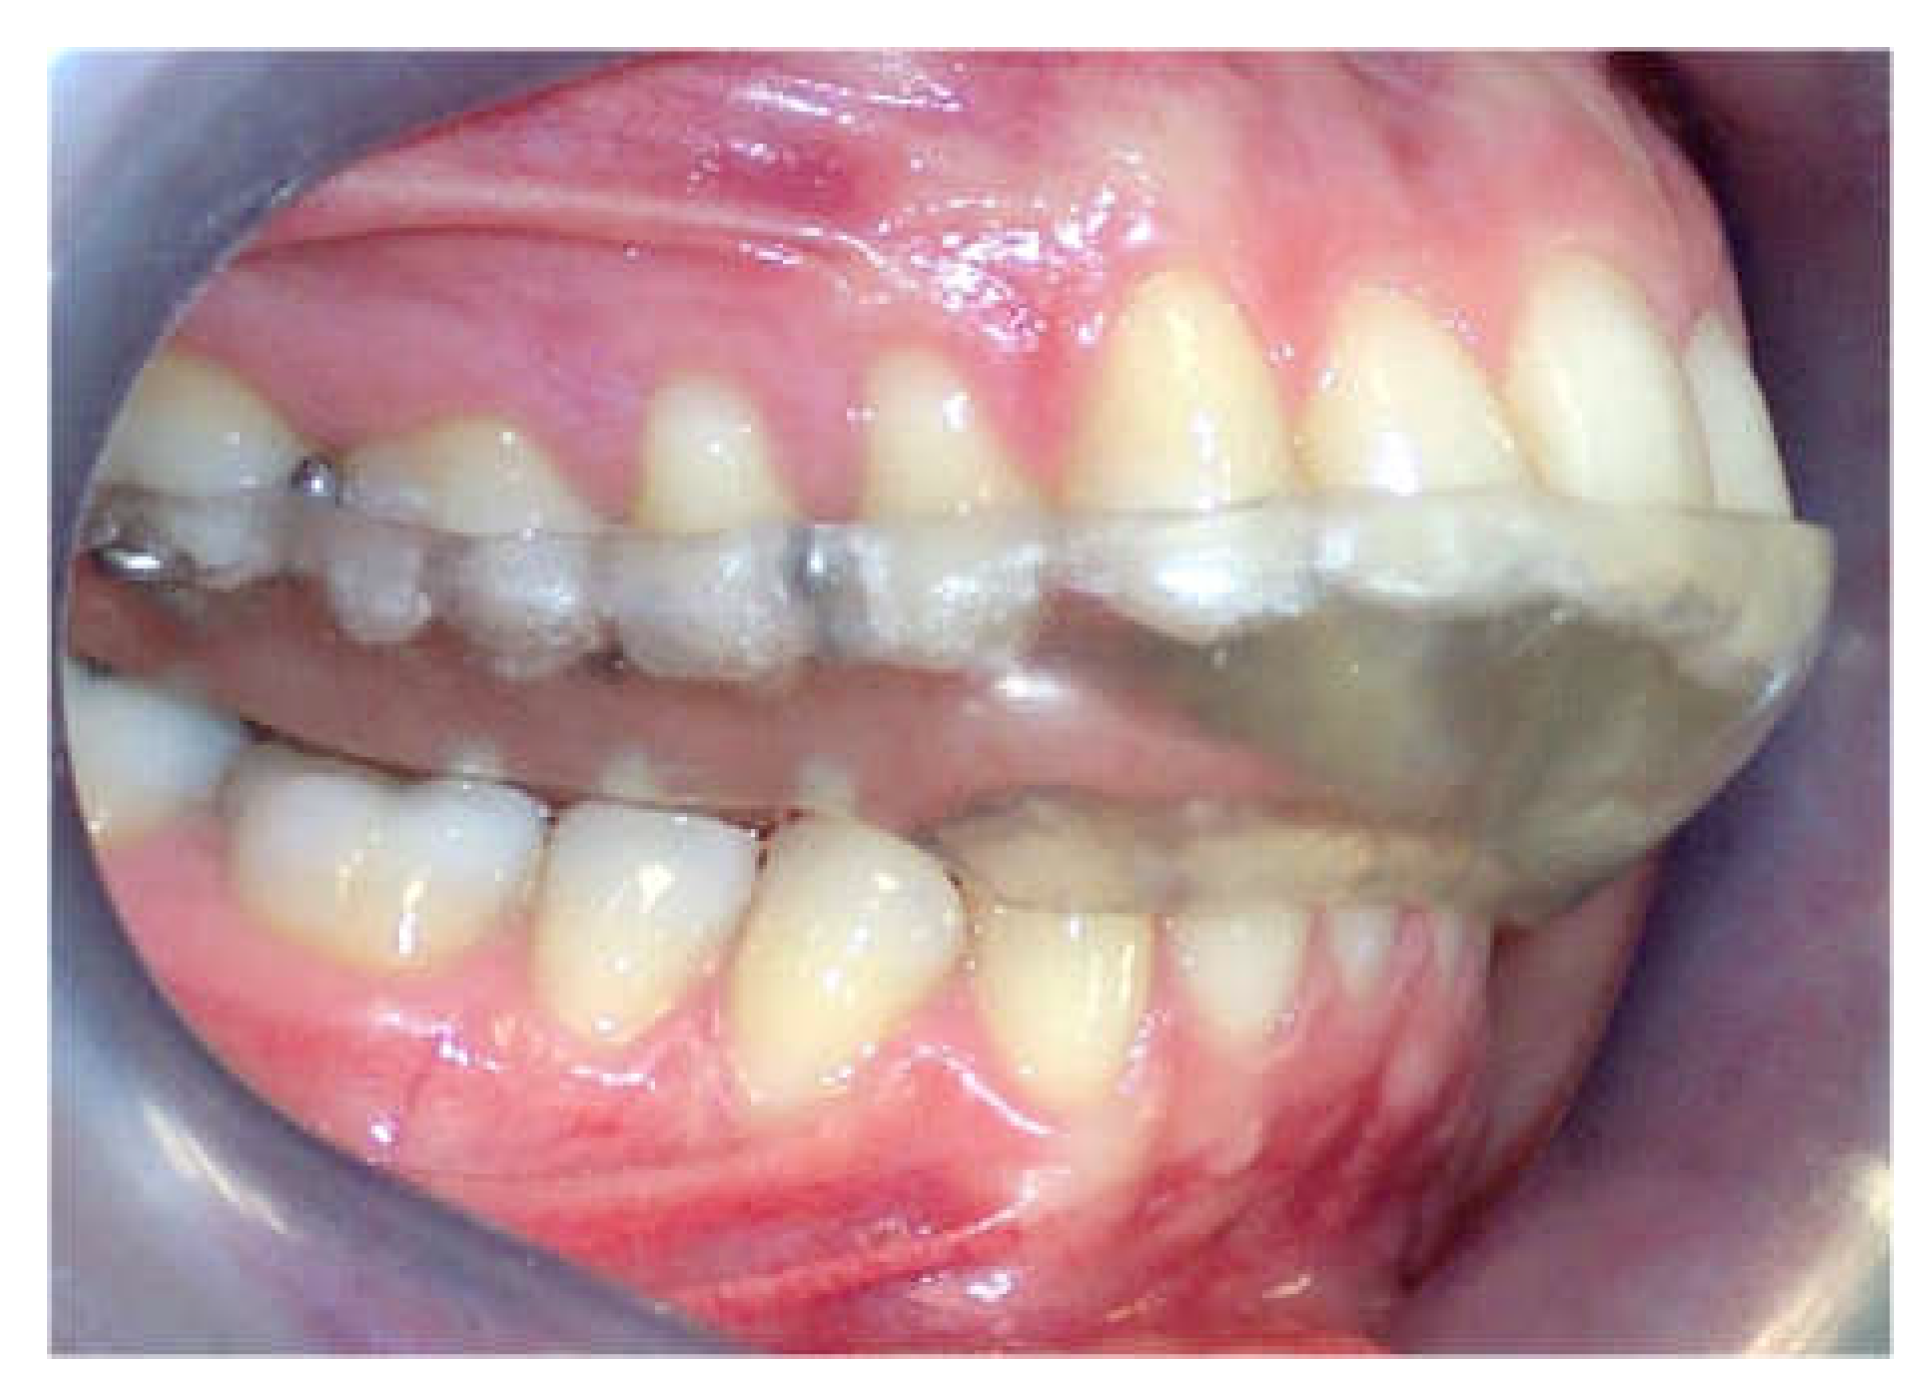

To assess the condylar position, diagnostic casts of all participants were mounted on a semi-adjustable articulator (Panadent Corp, Grand Terrace, CA, USA) using an estimated face-bow and CR bite registration taken with blue wax (Delar Corp, Lake Oswego, OR, USA) according to Roth’s power centric technique. To obtain a high degree of accuracy and verification of the articulator mounting, a split cast method was used. The anterior portion of the wax was folded in 4 layers over the incisor teeth region (canine–canine). For bite registration in the MI position, a single layer of hard pink wax (Beauty Pink Wax X Hard, Integra Miltex, York, PA, USA) was used. The mounted models were placed in a condylar position indicator articulator (Panadent Corp, Grand Terrace, CA, USA) to measure the amount of condylar discrepancy between the MI and CR positions using an initial MI and CR bite registration record. For the neuromuscular deprogramming, a hard acrylic stabilization splint was constructed according to the principles of a mutually protected occlusal scheme on models mounted in the CR position. All participants used the acrylic stabilization splint for approximately 6 months until a stable musculoskeletal position of the condyles in the CR was achieved (Figure 1).

Figure 1. Stabilization splint.